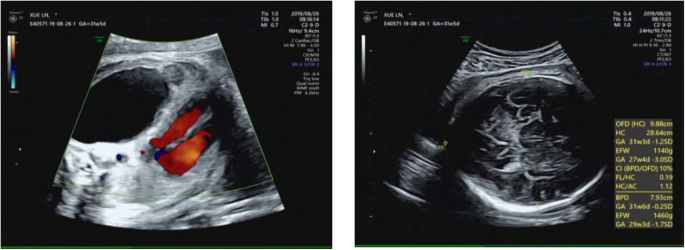

The child had healthy young parents and one older healthy sibling. At 30+ 2 weeks gestation, a routine antenatal ultrasound scan detected one echo-free cyst (5.4 cm × 3.3 cm × 5.6 cm) with a blood flow signal from the pulmonary circulation (Fig. 1). The CVR was 1.82.

The abnormality was judged as consistent with a macrocystic congenital cystic adenomatoid malformation of the lung situated in the left lower thoracic cavity, and this abnormality led to a significant shift of the mediastinal structures to the right side. Repeated ultrasound scans during pregnancy showed that the malformation grew (Figs. 2, 3).